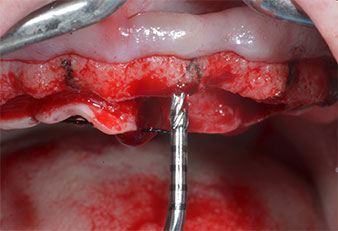

Пиезоелектрически инструмент с диамантено покритие с форма на пламък (Piezomed I1) e използван за маркиране на позициите на имплантите и за пилотна подготовка (Фиг. 3). Препарацията беше извършена с внимателни вертикални движения, с намалена мощност, пълна иригация и лек натиск (под 300 g) След това се приложи пилотен инструмент (Piezomed I2A/ I2P) за първоначално увеличение на диаметъра на имплантното ложе с 2 mm (Фиг. 4), последвано от 3 mm разширение (Фиг. 5)